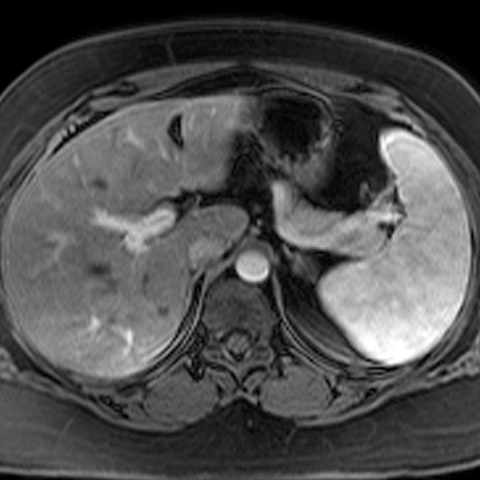

Normal Pancreas, Axial MRI [1 of 3]